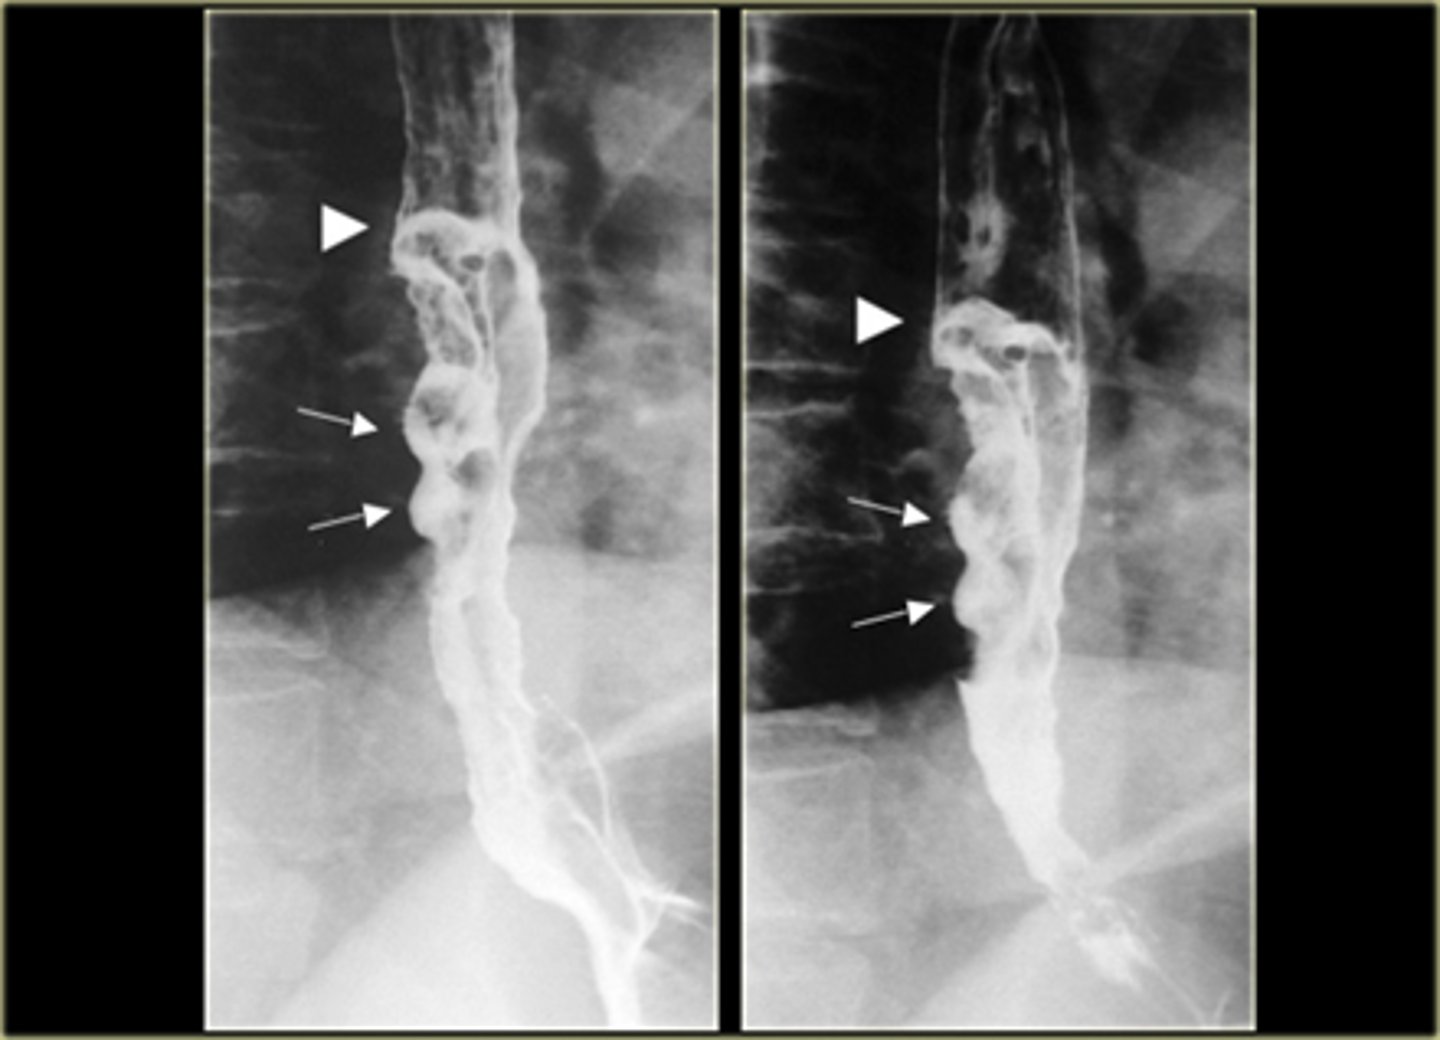

Esophageal carcinomas.

(A)

DOTTED BLACK ARROW:

annular constricting lesion of the midesophagus.

The tumor encircles the normal lumen and obstructs it in this case.

(B)

BLACK ARROW: Polypoid mass that arises from the right lateral wall of the esophagus and displaces the barium around it.

(C)

BLACK ARROW - wall, irregular and rigid

WHITE ARROW: a small ulceration (white arrow).